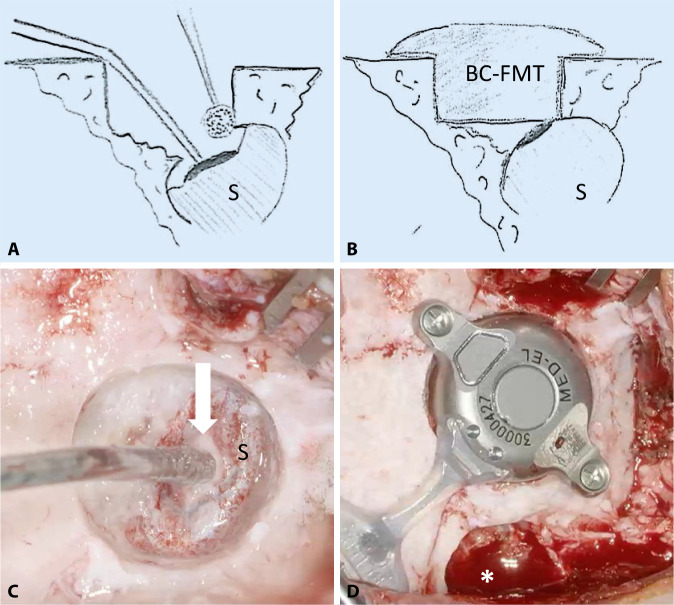

Figure 8 shows the preoperative planning for an adult patient with bilateral complex malformation and after previous hearing rehabilitation with a percutaneous bone conduction hearing implant on the right side (BAHA, Cochlear, Sydney, Australia) and a transcutaneous system on the left side (BCI 601). The patient had experienced recurrent skin irritation around the abutment, including skin overgrowth; therefore, the percutaneous bone conduction system on the right side was replaced with a BCI 602. Detailed preoperative CT-based planning was required due to scars from the previous skin incisions, the plan to simultaneously explant the fixture, and the presence of mastoid hypoplasia. Placing the BC-FMT required limited exposure and temporary impression of the sigmoid sinus (Fig. 9). By pressing the bony island of the sinus inward with a suction tip, it could be protected while the BC-FMT implant bed was molded with the burr. This technique can also be applied to avoid injury to the dura.

Fig. 9.

Placing the bone conduction-floating mass transducer (BC-FMT) close to the sigmoid sinus. A, C Due to the close proximity of the sigmoid sinus (S), a bony island is created on the exposed sinus wall (white arrow). This can be used to protect the sinus from the drill bit by temporarily and gently pressing on the island with the suction tip. B, D Final position of the BC-FMT after removing the pre-existing fixture (asterisk)